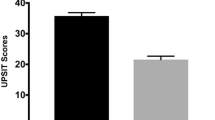

There were no significant group differences in performance on all cognitive tests, except the Symbol-Digit Modalities Test (SDMT, p < 0.05). Post-hoc analysis showed that hypos-PD patients performed worse than HCs on this test, but no difference was found between the two PD groups and between norms-PD and HC groups. As expected, a significant group difference was found in olfactory function (p < 0.001). Post-hoc analysis indicated that both HCs and norms-PD patients had higher University of Pennsylvania Smell Identification Test (UPSIT) scores than hypos-PD patients, whilst no significant difference existed between the former two groups. In addition, no significant differences were noted in disease duration, Hoehn & Yahr (H&Y) staging, and motor severity between the two PD groups. Detailed demographic and clinical data and statistics are presented in Table 1.

Graph-theoretical analysis

The overall topology of the networks showed that significant group differences were found to be in global efficiency (p = 0.001) and local efficiency (p = 0.026). Post-hoc analyses showed that compared with the HC group, the hypos-PD group had significantly decreased global efficiency and local efficiency (p < 0.01 and < 0.05, respectively), and the norms-PD group exhibited significantly reduced global efficiency (p < 0.01) but only slightly reduced local efficiency (p = 0.052). No significant differences were found between the two patient groups and in other graph theoretical metrics. Figure 1 presents the box plots of group averages of the graph-theoretic indices.